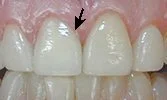

Before: This tooth has a large filling as shown. A crown is needed on this tooth, instead of a veneer, because there isn't enough natural tooth left to support a veneer. A crown will cover and protect the tooth, but will look the same as a veneer.

After: The top teeth now have veneers, except the one that had the large filling, which now has a crown.